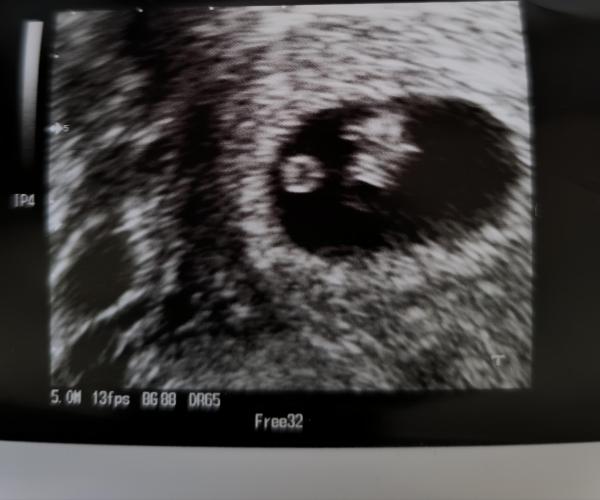

Hallo liebe Mitglieder, ich hatte heute meinen 1. Ultraschall đŸ„° datiert wurde ich auf die 7. SSW.    Kennt sich wer mit der Ramzi Methode aus? Ich weiß leider nicht, wo ich das genau fragen sollte 😅

Hab was gefunden: Die Ramzi-Methode – benannt nach ihrem BegrĂŒnder Saad Ramzi Ismail – besagt, dass sich das Geschlecht eines Embryos zwischen der 5. und 8. Schwangerschaftswoche anhand der Position des Nabelschnuransatzesvoraussagen lasse. Befindet sich der Ansatz der Nabelschnur auf der rechten Uterus-Seite, soll es sich um einen Jungen handeln. Entstehen Nabelschnur und Plazenta auf der linken Seite, bekommst du laut der Ramzi-Methode ein MĂ€dchen.

Puhh, schwierig zu erklÀren. Unterscheidet sich auch nach Bauch-US oder vaginalen US. Ist die Plazente (verdickte GebÀrmutterschleimhaut) auf der linken Seite, wird es ein Junge, bei der rechten Seite ein MÀdchen. Maggiiee_yt hat das auf YouTube ziemlich gut erklÀrt. ;)

Hab ich verwechselt, ja bei der linken Seite ein MÀdchen und bei der rechten Seite ein Junge. :D  Beim Bauch US einmal auf den Kopf drehen das Bild.

Bei mir wurde vaginal geschallt đŸ„° kennst du dich ein wenig damit aus? Laut der Platzierung könnte es ein MĂ€dchen werden đŸ„°